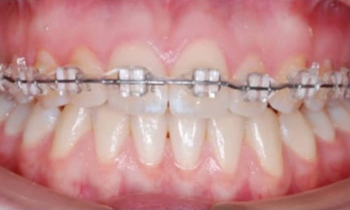

Наш ортодонт Евгений Владиславович Алексеев использует в своей работе не только стандартные общепринятые методики, но и самые современные, такие как аппарат Марко Роса